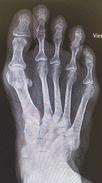

EAST COUNTY OBSERVER | THURSDAY, OCTOBER 6, 2022 5AYourObserver.com 389926-1 BUNIONS? Lapiplasty® by Limon fixes the root of the problem, addresses all 3 dimensions and you can walk within days of surgery! Dr. Lisa Griffith-Limon DPM, D-ACFAS is a Centurion Lapiplasty® Specialist: An honor only awarded to surgeons who have completed over 100 Lapiplasty® procedures!BEFORE AFTER ü Returns entire bone to normal alignment; a 3D correction ü Secures the root cause; an unstable joint ü Get back on your feet quickly in a boot; many cases within 2 weeks MOST INSURANCE ACCEPTED OPEN BY APPOINTMENT 11065 Gatewood Dr, Bldg C2, Lakewood Ranch 4614 26th Street W, Bradenton Serving Manatee County since 1998 Schedule to see if it’s right for you! 941.782.8639 LimonsFoot.com • Hundreds of home sellers like you have saved over $2.6MM with REALean! • Keep more of your home’s equity! • 21 Years experience, integrity, knowledge and detailed care. • Call me today to find out what your home is worth in today’s market! Home Sellers... Karen Nasello, Realtor since 2001 941-219-5959 Karen@Realean.com How would you like to pay ONLY 4% or less* to sell your home, while enjoying CONCIERGE-LEVEL Full Service? *3% if I am the only agent involved in the sale. New Listing Country Club East - Coach Home $758,900 Saving Sellers over $15,000 SOLD Tierra Verde - Lux Waterfront $2,150,000 Saving sellers over $40,000 382416-1 374085-1 HURRICANE SUPPORT NEEDED Cat Depot is in need of hurricane recovery support. Cash donations, cat food, or anything on our wish list would be much appreciated. 941-366-2404 | 2542 17th St., Sarasota, FL 34234 Donate today at www.catdepot.org 379617-1 to life preservers and guided them to higher ground.